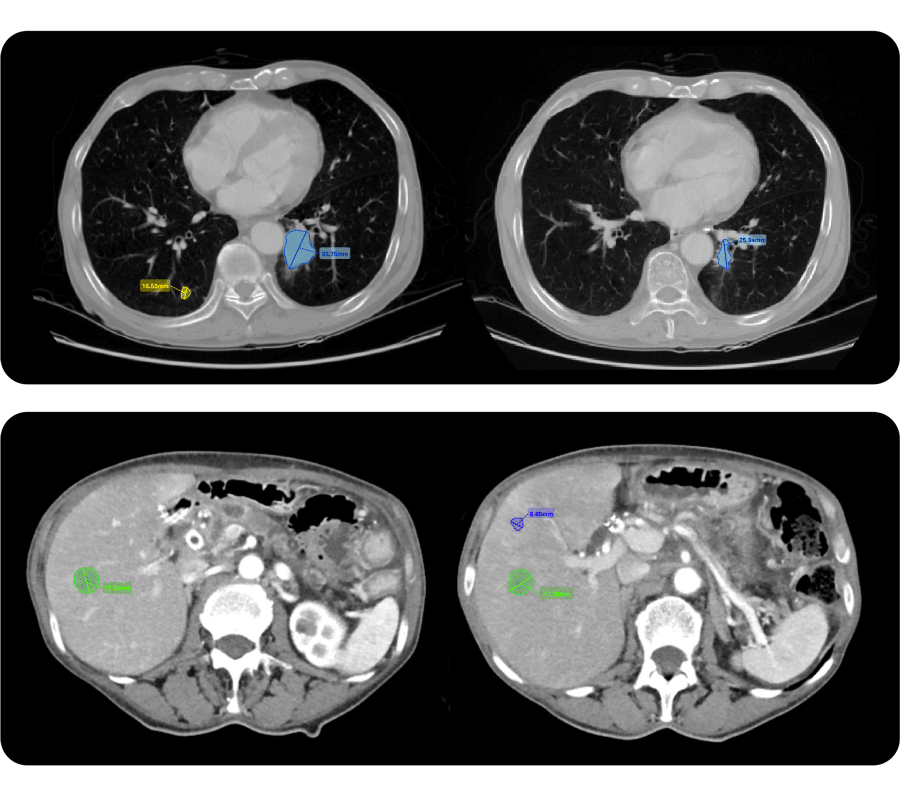

1. AI-supported lesion-assessment tool

Automatically detected, segmented, and measured target lesions of a patient with advanced NSCLC at baseline [left] and 1st on-treatment scans [right]

Quibim’s tools automatically identify, segment, measure, and track lesions throughout the clinical trial. By streamlining these processes, faster and less variable radiological assessments are enhanced to achieve more consistent interpretations. Experts can also manually segment or adjust automated results within an integrated DICOM viewer, supporting RECIST 1.1 and its variations without compromising workflow efficiency.